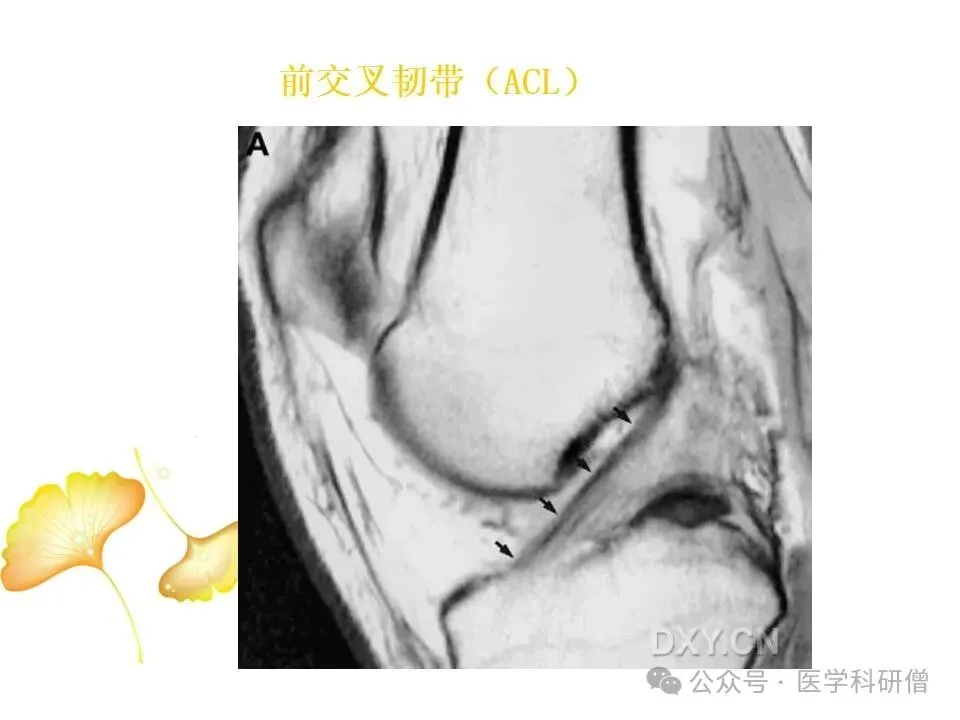

• 前交叉韧带(ACL):位于膝关节内部,负责防止胫骨向前滑动以及控制膝关节的旋转运动。

MRI是一种先进的医学成像技术,能够提供高分辨率的膝关节图像,对韧带损伤的诊断具有重要价值。MRI检查可以采用不同的成像技术,如:

• T1加权像:能够清晰显示韧带的解剖结构,帮助医生观察韧带是否完整、是否有撕裂的迹象。